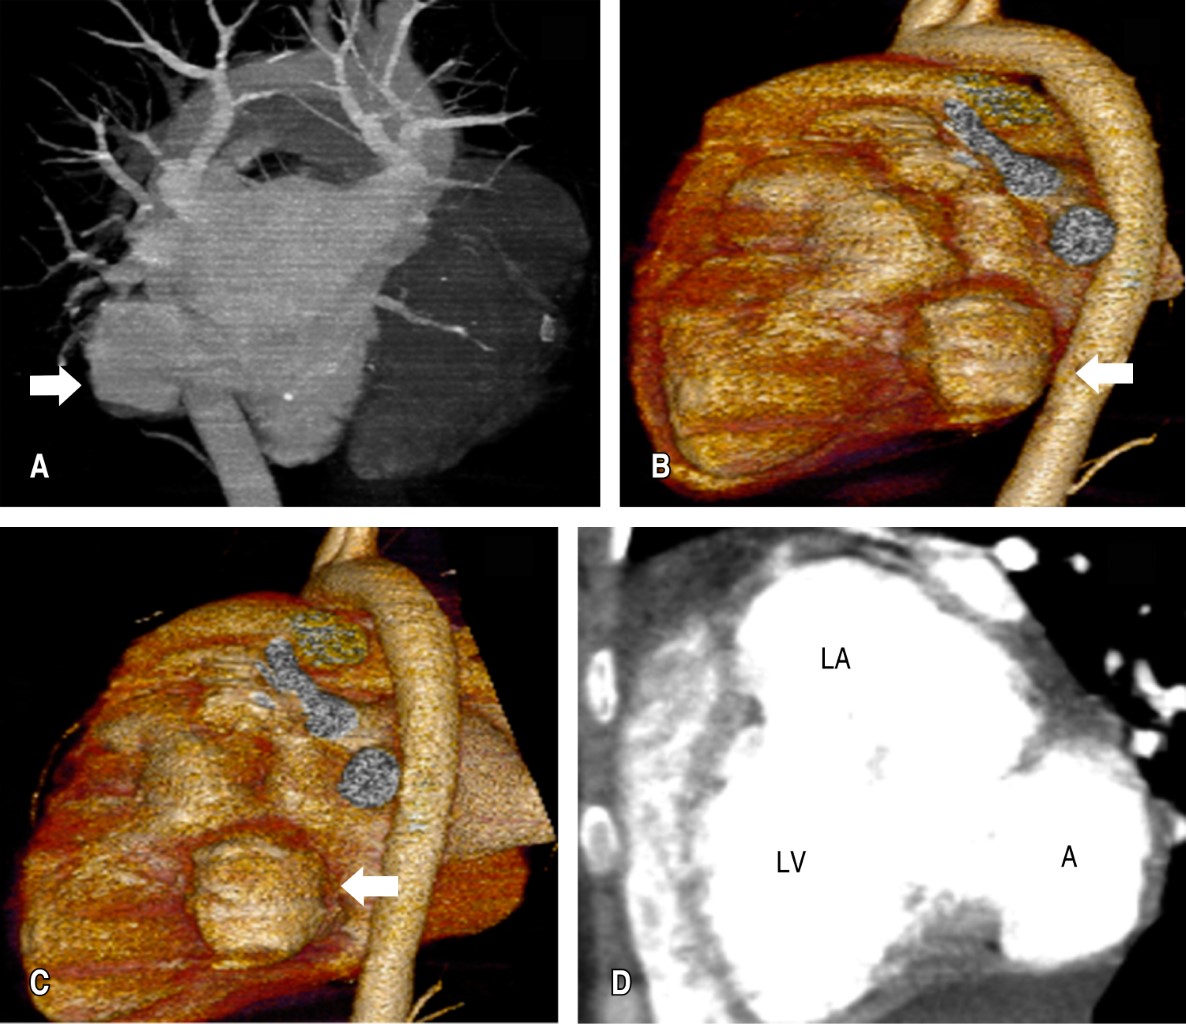

Aneurisma de presentación como causa de insuficiencia de la válvula mitral

Antunes-Vicente MB, Alarcón CH, Ravelo-Dopico R, Lima-Domingos LM, Méndez-Peralta T, Pedro A

Aneurisma ventricular cardiaco, aneurisma subvalvular mitral, insuficiencia valvular, falla cardiaca, cardiopatía congénita.

El aneurisma ventricular subvalvular mitral se considera una rara afección cardiaca con un origen aún no bien definido. Desde su primer informe por Corvisart en 1812, varios informes han coincidido en señalar su mayor incidencia entre los africanos, lo que ha sido escenario de varias discusiones hasta hoy. Existen varias controversias en torno a este tema, el consenso actual es de varios factores interrelacionados como la debilidad del anillo fibroso posterior de la válvula mitral está en la base de su aparición que puede ser de base sostenida, aneurisma congénito, procesos infecciosos, inflamatorios o degenerativos que involucran el endocardio. El diagnóstico de certeza se realiza mediante ecocardiograma y el tratamiento es eminentemente quirúrgico. Se describe el caso de una paciente de 28 años, de nacionalidad angoleña, con aneurisma subvalvular mitral como causa de regurgitación mitral severa e insuficiencia cardiaca, que fue corregida quirúrgicamente con éxito.

Figura 1